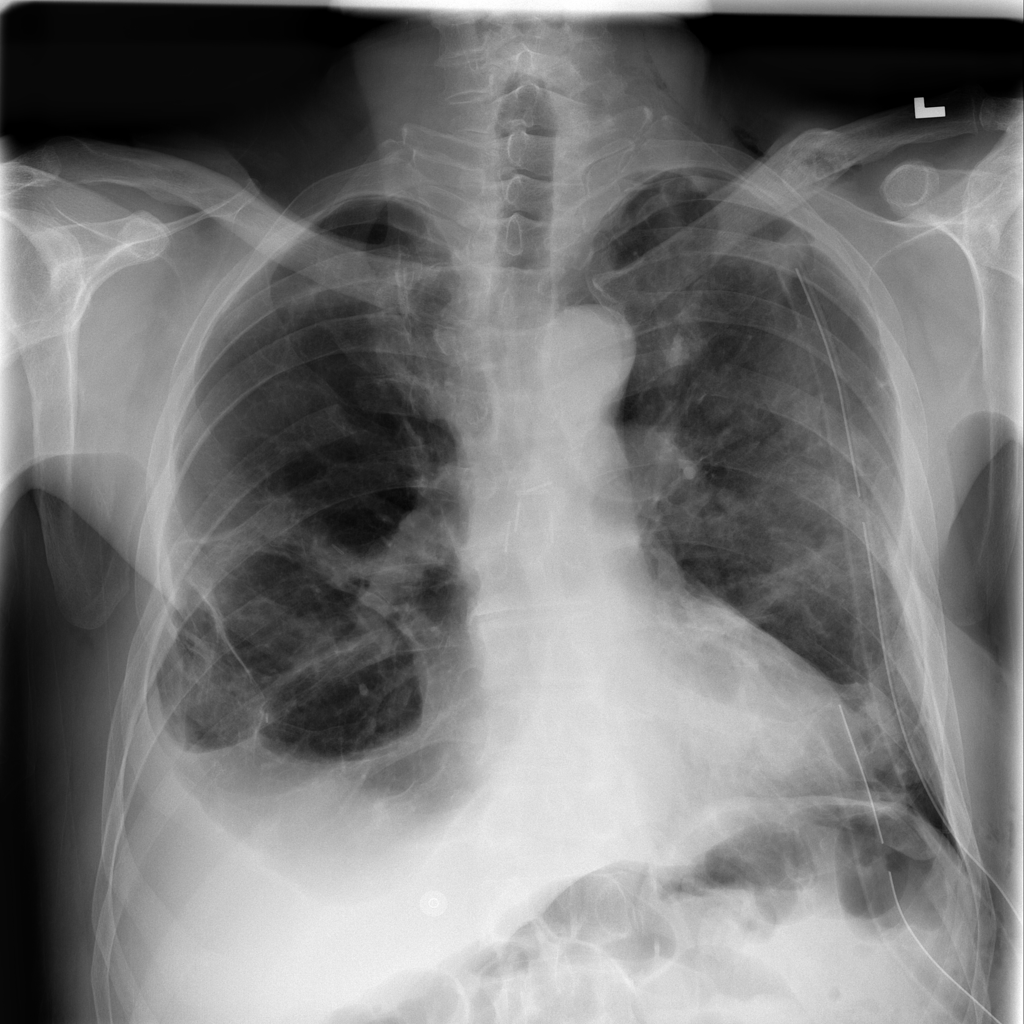

PAT-4639 · IMG-013Pneumothorax

PAT-4639 · IMG-013

AP